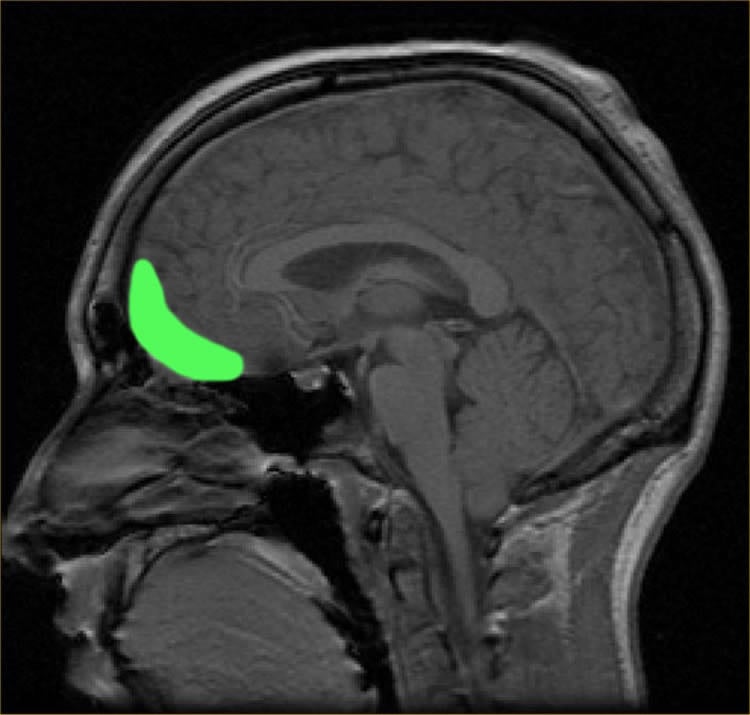

A study from Massachusetts General Hospital (MGH) researchers finds that the brains of young adult marijuana users react differently to social exclusion than do those of non-users. In a report published in the March issue of Biological Psychiatry: Cognitive Neuroscience and Neuroimaging, the team reports that activation of the insula, a region of the brain that is usually active during social rejection, was reduced in young marijuana users when they were being excluded from participation in virtual game of catch.

MR images taken during the Cyberball task focused on three brain regions that previous studies have associated with the response to social exclusion – the anterior insula, the ventral anterior cingulate cortex (vACC) and the orbitofrontal cortex (OFC). Since the OFC showed no significant activation during the task in either group, only results of the other two regions were analyzed.

While both the vACC and the insula showed activation during exclusion in the non-using control group, among marijuana users exclusion from the game produced no significant activation in the insula. Users exhibited the same level of vACC activation during exclusion as seen in the non-users, but an association between the amount of vACC activation and the levels of peer conformity and suggestibility measured on tests taken before the Cyberball task was only seen in marijuana users, not in non-users. The authors note that a greater susceptibility to peer influence in marijuana users could signify a more immature pattern of brain development.